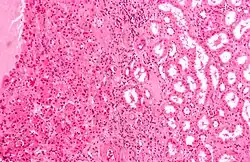

![]() | |

| Micrograph of a renal oncocytoma, a type of benign kidney tumour. H&E stain. | |